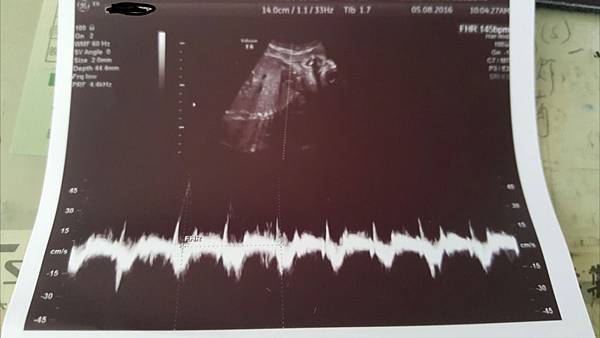

強而有力的心跳145下/分鐘不過技術人員說是148快接近男寶寶的心跳了

記得當初萱是140而已